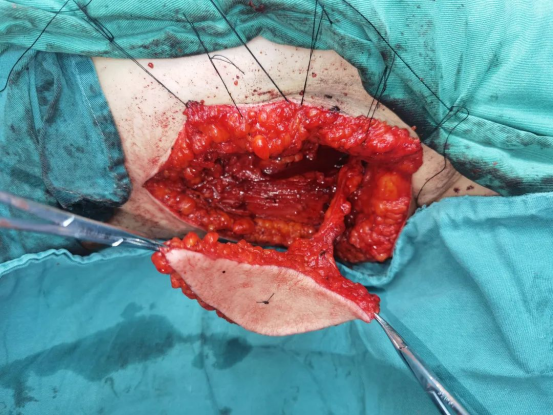

术中在颈部设计切口完成右侧功能性颈淋巴结清扫,在右侧下颌骨舌侧切开口底肌肉,将舌体从口内经颌下牵出,直视下切除右侧原发灶及右侧舌外肌,完成右侧舌颌颈联合根治术。这样既能在直视下切除原发灶,又能避免切开下唇,减少患者术后瘢痕对美观的影响。

术中图

在麻醉医师和手术室医护人员的共同努力下,刘睿医师团队历经8小时,按计划顺利完成手术。经过口腔颌面外科全体医护人员的精心治疗和护理,患者口内皮瓣愈合良好,舌体活动度良好,语音及进食功能无明显影响,口内外伤口均恢复良好,患者顺利出院,并对治疗效果表示非常满意。